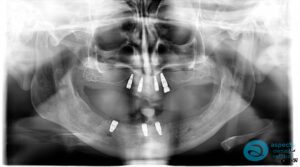

After Implant-Retained Overdentures Xray – Dental Implants Milton Keynes – Aspects Dental Case Study 19